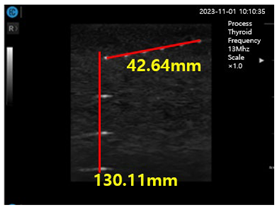

Figure 15a shows ultrasonic gel testing at various time intervals using the ATS-539 phantom. Figure 15b shows the sharpness of the image of the manufactured gelatin soft gel after storing it in alcohol and performing a sharpness test at 1 h intervals for 72 h. The results are presented in Figure 15b. In this paper, the experiment using a soft solid gel did not require IRB agreement. This research on the proposed gelatin soft solid gel showed its functionality to be better than that of ultrasonic gel, including on grayscale, echo, and color. This means that it can overcome the tissue density dead zone to increase high resolution performance. To help imaging accuracy, it is proven that gelatin soft gel, especially the soft solid gel, can replace ultrasonic gel to simplify disinfection and ensure permanent use. Image corrosion testing of gelatin soft solid gel for 30 min is shown in Figure 16a. Ultrasonic gels were tested at different times using an ATS-539 phantom, where the gel was soaked in ethanol for 72 h, as shown in Figure 16b. Afterwards, the gel’s condition was tested again. Finally, Figure 16c measures the imaging resolution of the gelatin soft tissue gel.